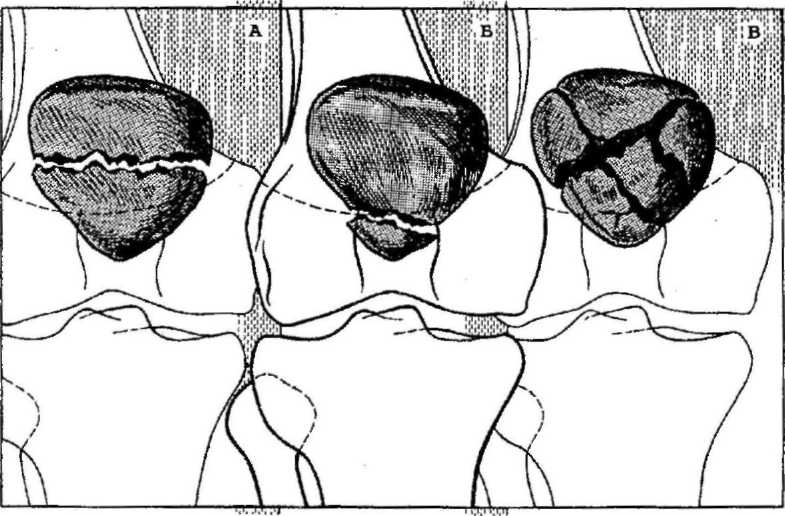

Варианты перелома надколенникаЧаще всего встречаются горизонтальные переломы. Так как к верхней части надколенника крепится сухожилие четырехглавой мышцы, которая тянет надколенник вверх, то, как правило, костные отломки разобщаются и между ними появляется щель. Такой перелом уже называется переломом со смещением.

Как мы уже отмечали, может произойти и отрыв нижнего края надколенника. При таком варианте линия перелома проходит в самом низу надколенника, там, где на его внутренней поверхности уже нет хряща.

Если удар будет высокоэнергетическим (то есть большой силы и с большой скоростью) то может возникнуть многооскольчатый перелом, который также может быть как без смещения, так и со смещением отломков.

Особый вариант перелома – вертикальный, при котором линия перелома проходит сверху вниз. В подавляющем большинстве случаев такие переломы не смещаются, так как тяга мышцы направлена снизу вверх, то есть вдоль линии перелома. Однако мировой медицине известны и редкие случаи смещения таких переломов, которые могут возникнуть в том случае, когда например, мыщелки бедренной кости диспластичны и надколенник изначально был смещен в сторону (обычно кнаружи).

И, наконец, может возникнуть и так называемый остеохондральный перелом, когда отрывается кусочек от суставной поверхности.